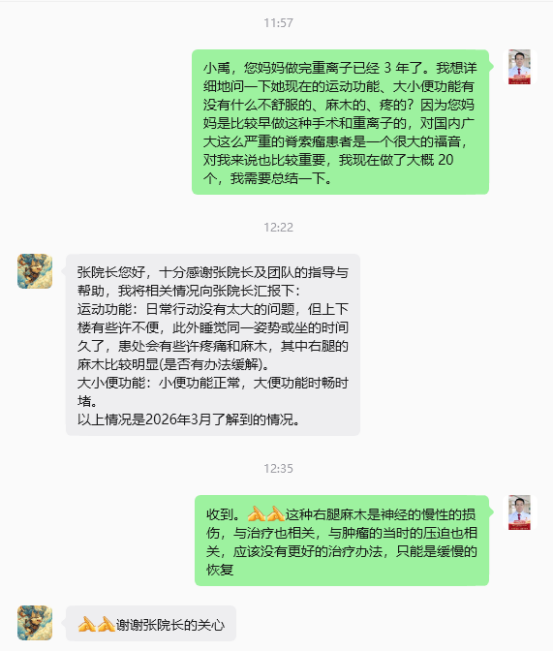

治疗后三年,肿瘤继续吸收变小了,患者的二便功能和运动运动恢复的很不错,疼痛于治疗后一年后明显缓解并缓慢悄失。